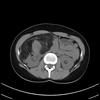

what syndrome is this. What are the 3 main features of the syndrome. What is the risk of x cancer.

Birt-Hogg-Dubé syndrome

Dr Patrick Rock◉ and Dr Maxime St-Amant◉ et al.

Birt-Hogg-Dubé syndrome or folliculin gene-associated syndrome is a genetic multisystemic disease mainly characterised by:

multiple lung cysts and secondary spontaneous pneumothoraces

multiple bilateral renal tumours (particularly chromophobe renal cell cancer and oncocytoma)

cutaneous manifestations (angiofibromas, perifollicular fibromas, acrochordons, fibrofolliculomas, etc.)

Birt-Hogg-Dubé syndrome carries an estimated 25% risk of renal cell carcinoma 12.

Radiographic features

CT

Lung cysts in Birt-Hogg-Dubé syndrome are usually multiple and have a lower zone predominance 11. Cyst morphology tends to be variable within each patient, with cysts commonly oval or lentiform and septated when large 4. The presence of paramediastinal cysts when disproportionate in number or oval (floppy) in shape is another distinguishing characteristic 11.